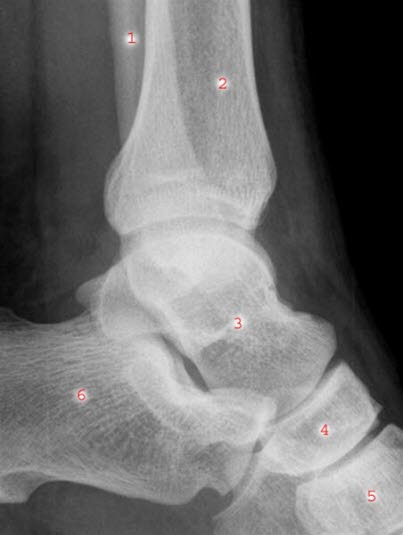

Ankelleddene er meget utsatte for skader fordi de er ganske bevegelige og belastes med hele kroppens tyngde. Leddet utgjøres av fire ben: skinnbeinet (tibia), leggbeinet (fibula), hælbeinet (calcaneus) og ankelbeinet (talus). Ankelleddet stabiliseres av ankelgaffelens form og leddbånd på innsiden (medialt), utsiden (lateralt) og mellom de to leggbeina (syndesmosen - et bånd som binder sammen de to beina). Se illustrasjon av ankelleddet nedenfor sett bakfra og fra siden, og røntgenbilde tatt skrått bakfra og fra siden.

Ved mistanke om brudd tas røntgenbilder av ankelen i ulike retninger. Det er viktig å ta bilde av fibula i hele sin lengde. Ofte foreligger flere brudd eller skader. Noen ganger er det nødvendig å ta CT for å klargjøre omfanget av brudd, særlig ved brudd i selve leddet.